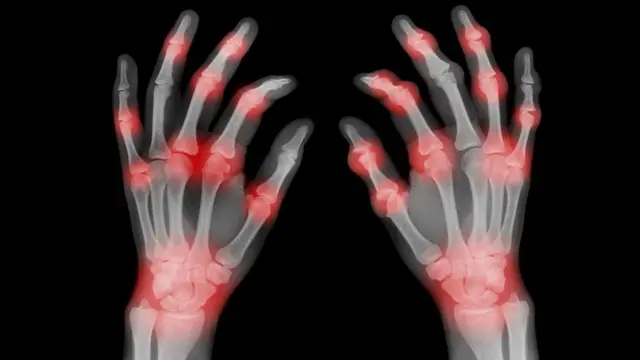

এই আবিষ্কারের পর বিজ্ঞানীরা বুঝতে পারেন, ক্যান্সার টিউমার অনেক সময় বিপুল পরিমাণ নিয়ন্ত্রক টি কোষকে নিজের দিকে আকৃষ্ট করে, ফলে সাধারণ টি কোষগুলো ক্যান্সার কোষ ধ্বংস করতে পারে না।

টাটা মেমোরিয়াল হাসপাতালের রক্তক্যান্সার বিশেষজ্ঞ ডা. হাসমুখ জৈন বলেন, “যখন কোনো টিউমারে অনেক রেগুলেটরি টি সেল জমে, তখন তারা অন্যান্য টি সেলকে ক্যান্সার কোষ মারতে বাধা দেয়। নতুন ক্যান্সার ইমিউনোথেরাপিগুলো এই বাধা ভাঙতেই কাজ করে—রেগুলেটরি টি সেলের প্রভাব কমিয়ে চিকিৎসার কার্যকারিতা বাড়ানো হয়।”

বর্তমানে বিভিন্ন ক্লিনিক্যাল ট্রায়াল চলছে, যেখানে চেষ্টা করা হচ্ছে রেগুলেটরি টি কোষের সংখ্যা বাড়িয়ে অটোইমিউন রোগ নিয়ন্ত্রণে আনা যায় কি না। একইসঙ্গে অঙ্গ প্রতিস্থাপনের পর অঙ্গ প্রত্যাখ্যান রোধে এই পদ্ধতি কাজে লাগানো হচ্ছে।